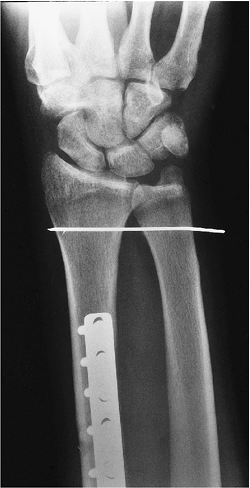

Fractures/Dislocations: Galeazzi Fractures

-

The Galeazzi fracture is a fracture of

the distal radius, usually diaphysis, with associated subluxation or

dislocation of the DRUJ. -

Mechanism of injury: fall on the outstretched hand with hyperpronation of the forearm.

Treatment: reduction and internal fixation.

Routine radiographs are diagnostic.

Complications: malunion of the fracture and residual subluxation of the DRUJ.

FIGURE 9-9 PA (A) and lateral (B) radiographs showing a distal radial fracture with dislocation of the DRUJ.

![]() |

FIGURE 9-10 PA radiograph after plate and screw fixation of the radial fracture and K-wire fixation of the joint.